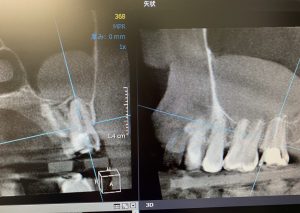

左上7番、根尖病巣が原因で副鼻腔炎を併発する状態に、、

幸にも鼻道と上顎洞(副鼻腔)を繋げる自然口が開いていて、上顎洞内の換気、排出のサーキュレーションは問題がないことから耳鼻科医師に対診をやり取りし、根管治療を開始しました。

治療4ヶ月間経過したところで粘膜肥厚していた上顎洞も治癒促進!

骨の再生も確認されたので、本日根管治療のファイナルMTAセメントにて根管内を充填。

画像CT.(上は今年8月-下は12月)